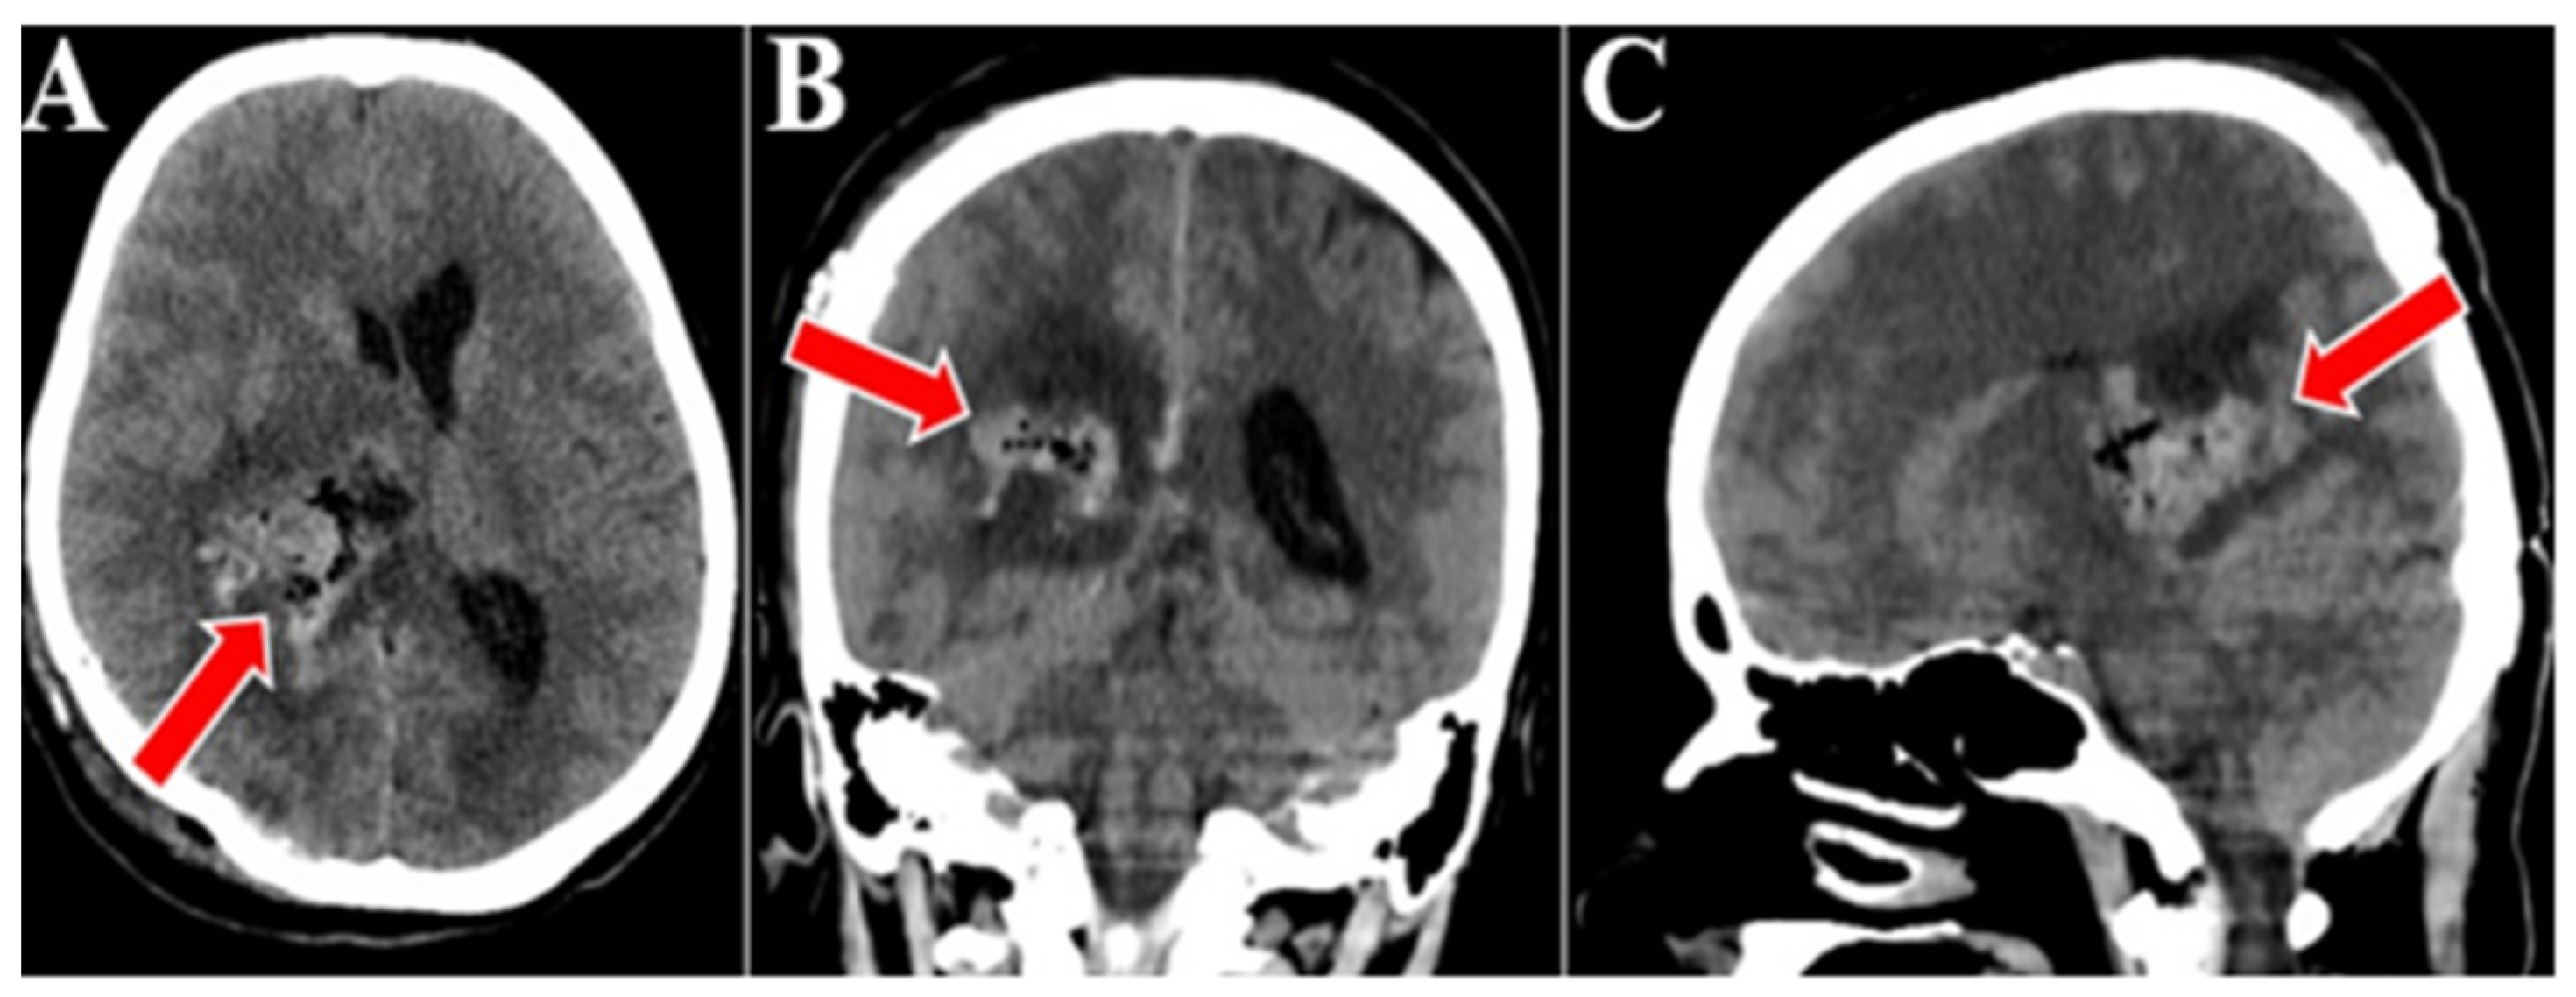

Figure 4. Postoperative CT scan, all three sequences, axial (A), coronal (B), and sagital (C). Postoperative CT scan that confirmed the gross total resection of the tumor, an area of right thalamic hypodensity and right deep parietal of sequelae aspect (red arrows).

Surgery was performed on the tumor, and gross total tumor resection was achieved, utilizing a parieto-occipital surgical approach on the designated side. The transcortical access was used to approach the neoplasm, subsequently followed by stepwise ablation under magnification with microsurgical tools. Efforts were made to preserve the vascular structures at the specific level, including the thalamostriate veins along with their tributaries, and the perforating branches emanating from the posterior cerebral artery that penetrate the tumor. A postoperative brain CT scan was conducted, which confirmed the quasi-complete resection of the tumor and an area of right thalamic hypodensity and right deep parietal of sequelae aspect. Otherwise, there was a normal cerebroventricular tomodensitometric aspect. There were no signs of bleeding in the tumor bed (Figure 4).